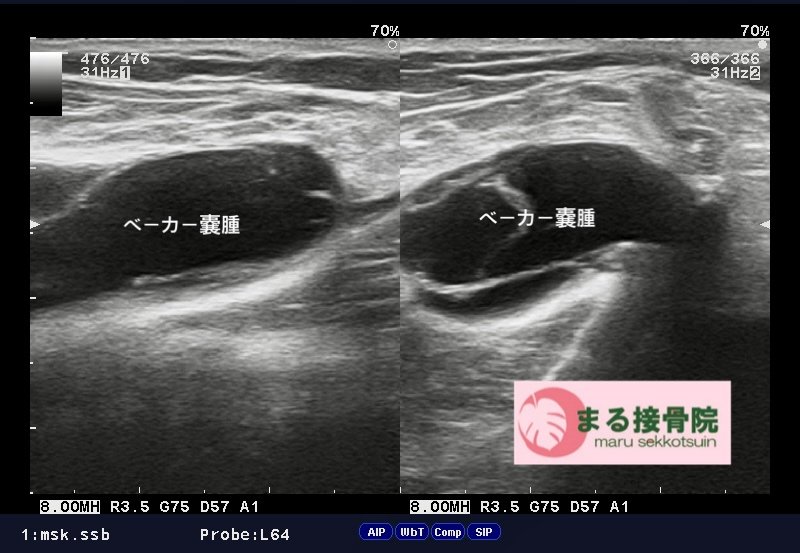

関節は関節包という袋で包まれており、その中は滑液という液体で満たされています。

ベーカー嚢腫とは、膝の裏にある滑液包に膝関節部の滑液が滑液包へ流れ込み、貯留して膨らんだもので、膝窩の内側で腓腹筋内側頭と半膜様筋腱の間に診られます。

初期症状は膝裏の痛み・違和感、日常生活や運動後などに、「膝の裏が腫れている」「膝を曲げると痛み・違和感がある」という症状で50代以降の中年女性に多く起こります。

また、膝関節部が腫れる変形性膝関節症・半月板損傷・関節リウマチ・関節炎などの、炎症反応により関節内部に多量の滑液が生じることで、ベーカー嚢腫が大きくなります。